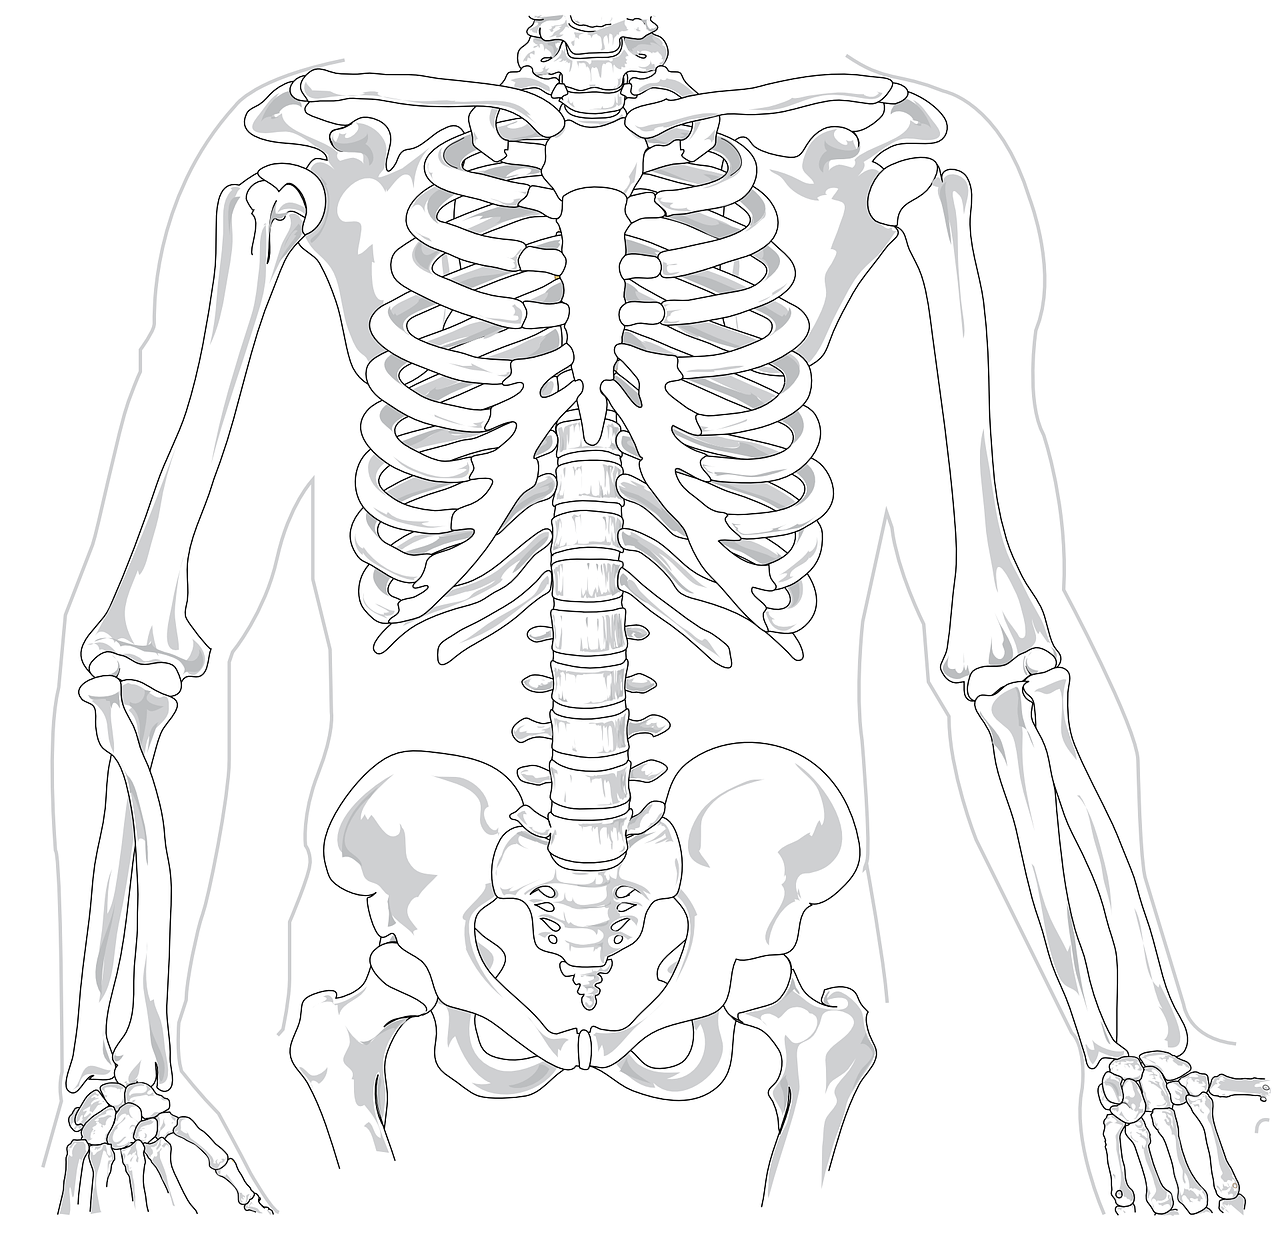

허리디스크는 척추 디스크가 손상되어 주변 신경을 압박하며 다양한 고통을 유발하는 질환입니다. 특히 허리 통증이 주된 증상이지만, 그 외에도 여러 증상이 나타날 수 있습니다. 아래 허리디스크 대표적인 5가지 증상을 알려드릴테니 확인해보시기 바라며, 허리디스크 자가진단까지 진행해보시길 바랍니다.

1. 허리통증

허리디스크의 가장 흔한 증상입니다. 아마 이 글을 검색해서 들어오신 분들은 모두 겪고 있으실거라 생각되는데요. 허리 부위에 지속적으로 발생하기도 하며 간헐적으로 통증이 심하게 찾아오기도 합니다.

특히 허리를 구부리거나 물건을 들어올릴때 통증이 가장 심하게 나타납니다.

허리 통증은 가만히 두면 더 심해질 수 있습니다. 따라서 적절한 치료나 운동이 필수입니다. 소개해드리는 곳을 참고하셔서 꼭 허리통증을 초기에 잡으시길 바랍니다.